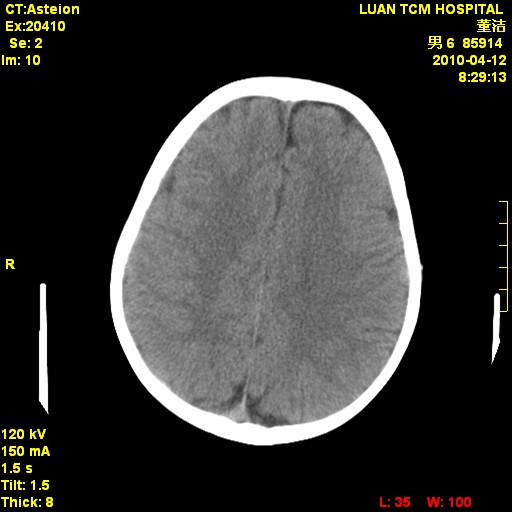

标题: PED3404:有结果,先猜猜这是啥病表现?男,12岁。 [打印本页]

标题: PED3404:有结果,先猜猜这是啥病表现?男,12岁。

右侧额顶部自颅板向内近似半圆高密度影,周围无明显水肿,考虑:脑外血肿?脑膜瘤?淋巴瘤?